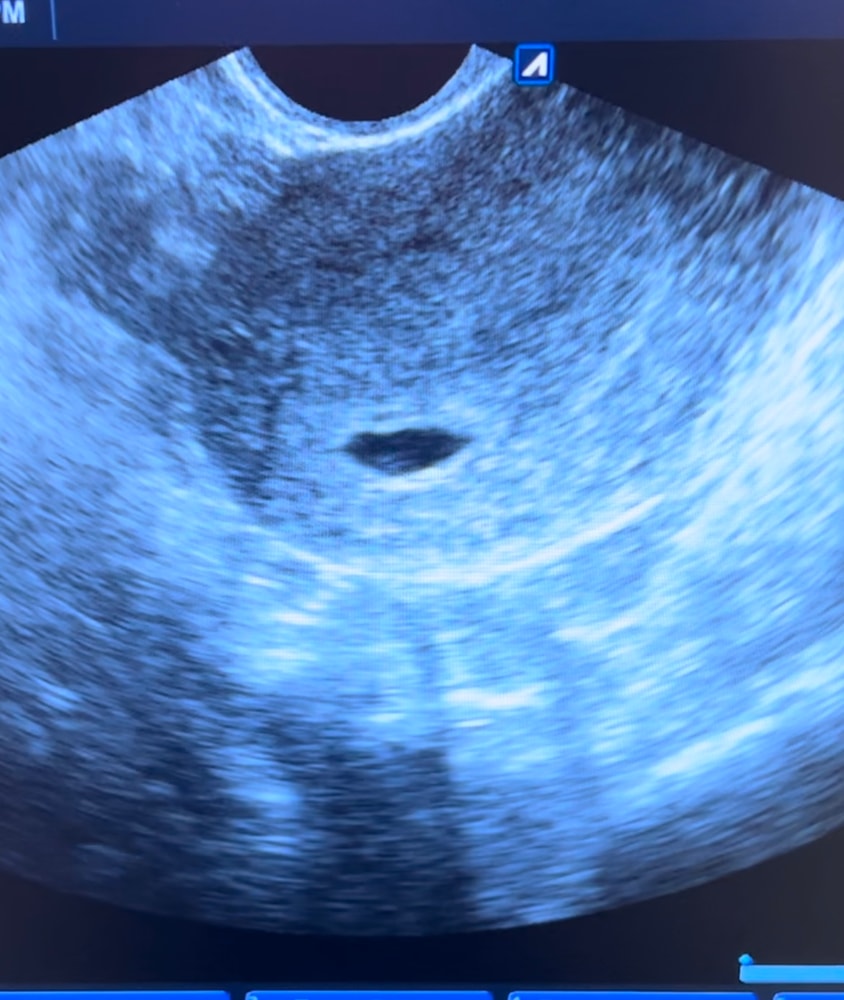

Как минимум плодное яйцо и желточный мешочек ) но статичному кадру плохо понятно, но если в динамике может уже мерцание сердечка было ? У эмбриончика . Тут не совсем хорошее качество узи)

Череппааашка по имени Натааашка , увидели пульсацию как мне сказали это был желточный мешочек, аппарат узи был достаточно старый, качество изображения не очень хорошее

Виктория Рыгина, ну пульсация только у эмбриона может быть ) у мешочка никак нет 😅эмбрион обычно сливается с контурами жм на ранних сроках и если аппарат плохой тяжело увидеть эти 0,5 мм . Через неделю уже точно подрастет )

Череппааашка по имени Натааашка , так то даже про эмбрион сказали что не понятно есть он или нет, контроль через неделю, очень переживаю